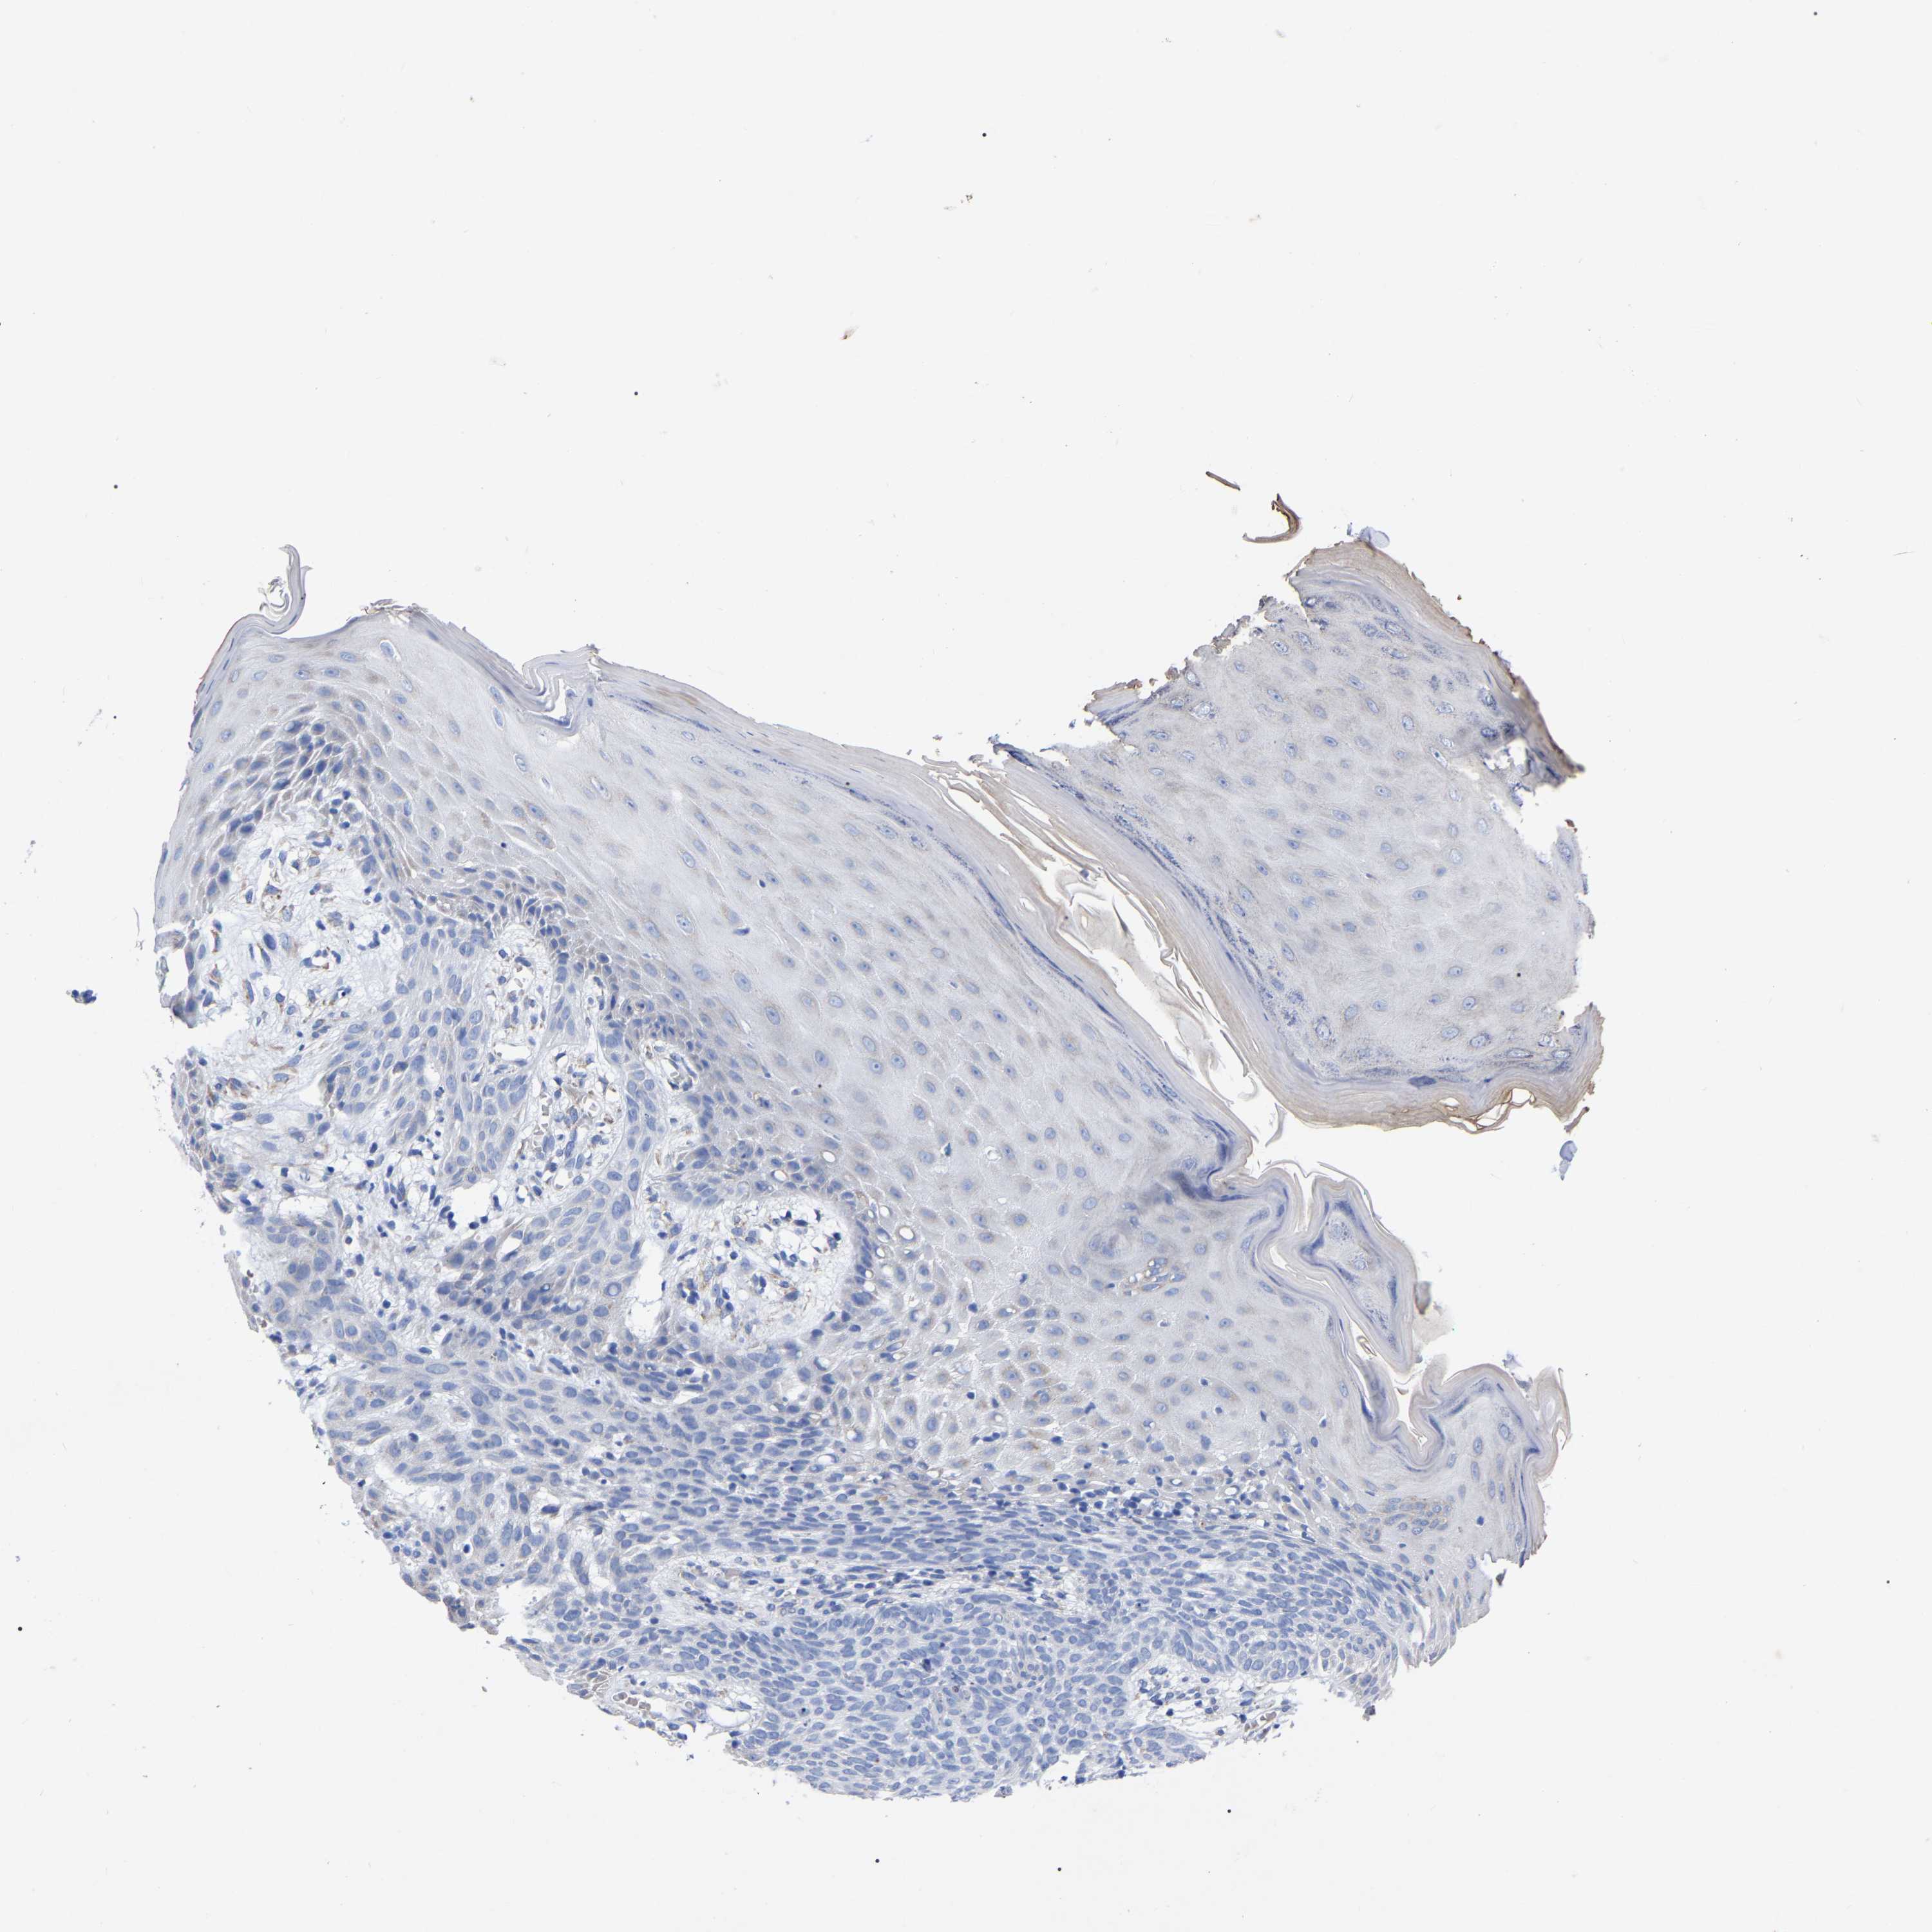

SKIN CANCER - Protein expressioni

A mouse-over function shows sample information and annotation data. Click on an image to view it in a full screen mode. Samples can be filtered based on level of antibody staining by selecting one or several of the following categories: high, medium, low and not detected. The assay and annotation is described here.

Each image is clickable and will lead to virtual microscopy that enables deeper exploration of all samples and also displays staining intensity scores, fraction scores and subcellular localization as well as patient and tissue information for each sample.

Antibody HPA018468

Squamous cell carcinoma in situ, NOS